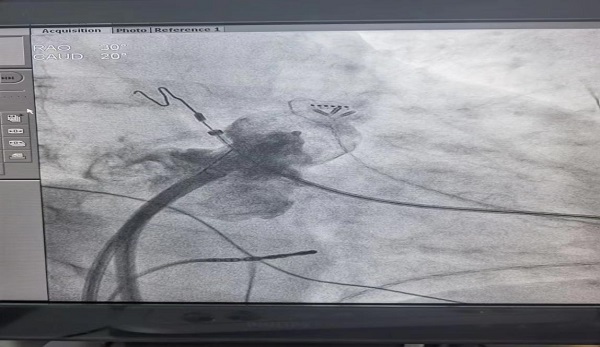

7月19日,二一五医院心血管内科二病区再次成功为一名阵发性房颤患者完成房颤射频消融+左心耳封堵术。

此一站式介入手术,由何亚军副主任主刀,何勇副主任医师配合完成,手术历时4个小时,术后恢复窦性心律,效果完美,患者目前正在顺利康复中。

左心耳封堵是一种微创介入技术,通过穿刺股静脉,把封堵器送至左心耳开口处,进行封堵,避免左心耳形成血栓,对于高栓塞风险、高出血风险的房颤患者是最佳选择。其优势为:1.无需开胸,微创手术。2.手术安全有效。3.不用长期服药:避免了长期抗凝引起的消化道和脑出血风险。